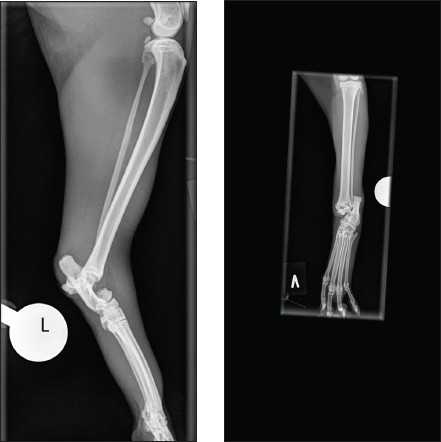

Fig. 1. (A and B) Mediolateral and craniocaudal digital radiography of the left hock joint. The talar neck fracture is evident, with luxation of both the tibiotalar and subtalar joints.

ABSTRACTBackground: Fractures of the talus are relatively infrequently reported in small animals. Furthermore, talar neck fracture in cats seems to be very rare. This case report aims to consider the diagnosis, treatment, and a 7-month follow-up of a cat with a Hawkins type 3 talar fracture treated with a type 1b external skeletal fixator (ESF). Emphasizing on the complexity of the injury, considering treatment options and complications, and comparing them to previous reports on cats and humans. Case Description: A 4.5-year-old mixed-breed cat was diagnosed with a Hawkins type 3 talar fracture. Additionally, there were considerations related to the collateral support of the hock joint. The fracture fragment, i.e., the talar body and parts of the neck, was reduced with pointed reduction forceps through a small medial insition. The fracture was then stabilized with a trans articular type 1b ESF. Based on radiographic fracture assessment, de-staging of the frame was done 8 weeks postoperatively. While complete frame removal was at 12 weeks postoperatively. Seven months after the fracture, the cat was minimally lame when walking, and there was a reduced range of motion in the hock joint compared to the contralateral joint. Conclusion: Based on this case and the four previous cases with talar neck fractures, we cannot conclude, but ESF seems to be a good solution, especially when considering the possibility of disruption to the collateral support of the hock joint in this case. Keywords: Cats, External fixation, Fracture, Talocrural joint, Talus. IntroductionThe tarsal joint consists of the tarsal bones and the joints between the crus and the metatarsus. Ninety percent of movement occurs in the tarsocrural joint (Carmichael and Marshall, 2018). The talus is the only bone that articulates with the tibia and fibula and is the most complex structure of all tarsal bones. Anatomically, the talus consists of the body, neck, and head, where the body is composed of the trochlea, which articulates with the cochlea of the tibia. The talar head articulates with the central tarsal bone (Vollmerhausl et al., 2002a). Furthermore, there is a strong articulation between the talus and the calcaneus (Vollmerhausl et al., 2002a, 2002b). The talus gets most of its blood supply from the dorsal pedal artery, a continuation of the cranial tibial artery at the level of the tarsocrural joint (Barnes, 1993; Lahunta et al., 2013). The supporting structures of the feline tarsal joint differ from those of the dog and have been well described (Young et al., 1993; Vollmerhausl et al., 2002b). Injuries to the talus are complicated because the bone is articular and plays a prominent role in the weight-bearing process (Carmichael and Marshall, 2018). Talar fractures are uncommon in cats and dogs, with talar neck fractures being extremely rare in cats (McCartney and Carmichael, 2000; Piermattei et al., 2006; DeCamp et al., 2016). In humans, talar fractures represent 0.1%–2.5% of all fractures and 3%–5% of foot and ankle fractures (von Knoch et al., 2007; Fournier et al., 2012; Lee et al., 2020). There is no current classification system for talar neck fractures in small animals, while in humans, talar neck fractures are classified after Hawkins, where Hawkin’s type 3 talar neck fracture is defined as displaced with subtalar and tibiotalar dislocation (Hawkins LG, 1970). This case report describes radiographical findings, management, and mid-term follow-up of a cat with a Hawkins-type 3 talar neck fracture (Cook et al., 2010). Case DetailsA mixed-breed spayed female cat, 4.5 years old and 5.2 kg, was seen at the out-of-hours service due to acute non-weight-bearing lameness of unknown cause on the left pelvic limb. This is a client-owned cat, and the owner signed a consent form approving all interventions mentioned here. Therefore, no further ethical approval was needed. The basic clinical examination and neurological examination were unremarkable. The cat was examined for evidence of other injuries apart from the limb. This included a general blood profile (hematology and biochemistry) and thoracic and abdominal radiographs, all unremarkable. The initial treatment was intravenous fluid (IV) 25 ml/hour (Ringer acetat, Fresenius Kabi) and analgesia in the form of 0.3 mg/kg/4 hours Methadone (0.3 mg/ml) intramuscular (IM) (Insistor vet, VetViva Richter Salfarm Scandinavia) and an initial dose of 0.3 mg/kg subcutaneously (SC) Meloxicam 5 mg/ml (Metacam vet. Boehringer Ingelheim Animal Health Nordics A/S). Finally, the affected leg was protected with a well-padded bandage overnight. After the first 24 hours, the meloxicam dose was reduced to half the initial dose. The following day, the cat was pre-medicated by adding Dexmedetomidine (0.5 mg/ml) at a dose of 20 µg/kg IM (Dexdomitor vet, Orion Pharma Animal Health) to the already provided Methadone. General anesthesia was induced with IV Propofol (10 mg/ml) (PropoVet Multidose, Zoetis Animal Health ASA) at a dose of 1.2 mg/kg to effect, and the cat was intubated and maintained on sevoflurane in 100% oxygen. Palpation of the affected leg revealed noticeable swelling and discontinuity of the hook joint. The fracture was closed, and orthogonal radiographs revealed a dislocated talar neck fracture, with tibiotalar and subtalar luxation (Fig. 1a and 1b). Based on the nature of the fracture, it was anticipated that there would be collateral support disruption. Fracture repair was performed using a routine aseptic hanging limb, ensuring intraoperative fluoroscopy could pass around the hock joint. An initial attempt at closed reduction of the fracture fragment was made but proved difficult. Therefore, a small medial incision was made, and the fracture fragment was repositioned using pointed reduction forceps and traction. The fracture was stabilized with a unilateral biplanar trans articular external fixator [External skeletal fixator (ESF) type 1b], using small treaded Elis pins, the Kirscher–Ehmer plus system (Veterinary instrumentation, Sheffield) drilled into the tibia, tarsal and proximal metatarsals through stab incisions, as previously described techniques for pin placements (Palmer, 1999; Kraus et al., 2003), using a battery-driven drill (Colibri II, Depuy Synths). The external fixation bars were contoured to approximately 125. The craniomedial and craniolateral incisions were closed routinely with poliglecaprone 25 4–0 (monocryl, Ethicone), and the total surgical time was 70 minutes.